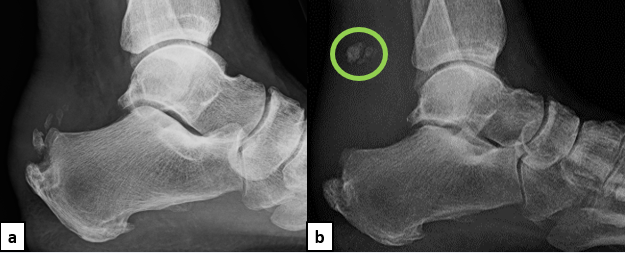

A healthy 66-year-old female who presented at our office via urgent care referral for a chronic left Achilles tendon rupture. She had been diagnosed by an another provider with Achilles tendinitis with retrocalcaneal spurring (Figure 1a) several months prior and had been working with physical therapy. She presented to urgent care with concern for possible deep vein thrombosis (DVT) as she experienced worsening calf pain while trying to walk for the previous couple of weeks. She had no recollection of a provoking injury, so the exact timing of rupture is unknown, but it likely took place about 7 weeks prior. Urgent care obtained updated radiographs and a magnetic resonance imaging (MRI) study (Figures 1b & 2).

The patient presented to our office with a palpable dell of the Achilles tendon extending from the insertion site to the mid-calf region. There was no plantarflexion with calf squeeze and the patient had a positive Thompson’s test. The patient elected to move forward with surgical intervention consisting of a flexor hallucis longus tendon transfer and open repair of the Achilles tendon rupture with bone-tendon allograft and remodeling of the posterior calcaneus.